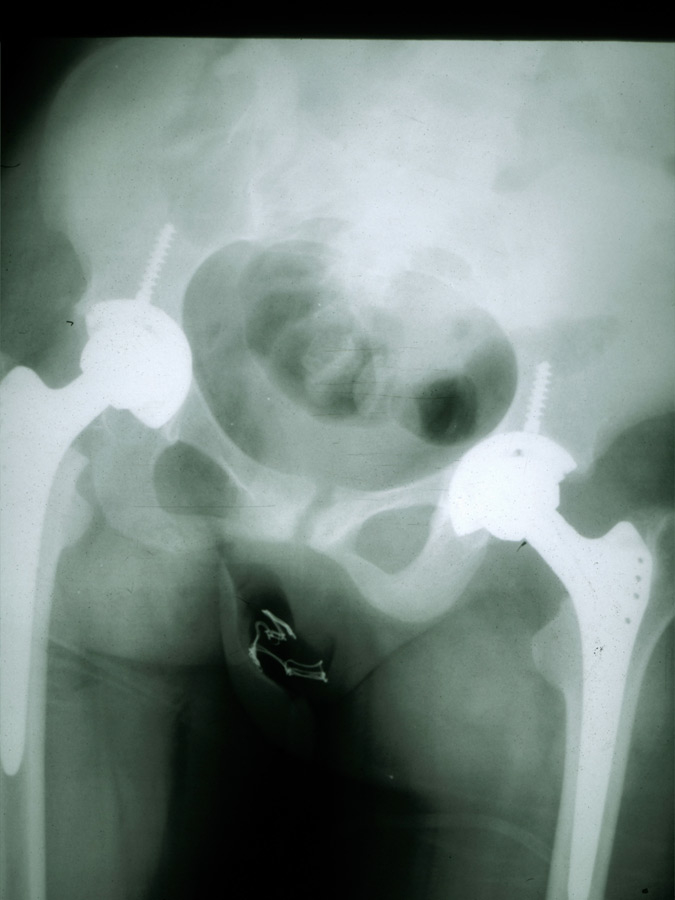

Figure 2

Hip replacement in a patient with SoJIA.

Any joint may be affected at disease onset, and involvement may be oligo- or polyarticular, but arthritis tends to increase in severity over time. In about a third of the patients, only arthralgia are reported at the onset of disease, and the presence of clear arthritis may be observed even years after the occurrence of systemic symptoms [4]. The typical spiking fever goes up to 39° or 40° once or twice daily and returns rapidly to 37° or below [6]. A persistent fever over 24 hours should suggest other diagnoses, or MAS complicating SoJIA [8]. An erythematous macular rash (salmon-pink coloured) often accompanies the fever; it is usually localised over the trunk and the proximal extremities, tends to be migratory, and may be urticarial or sometimes pruritic [9, 10]. Enlargement of the lymph nodes, the liver and/or the spleen may occur. In less than 10% of the patients a pericarditis will develop, often asymptomatic and only rarely inducing a tamponade [4, 11]. The two major complications of SoJIA are MAS and secondary amyloidosis [12]. MAS is a severe, potentially life-threatening complication characterised by the excessive activation of well-differentiated macrophages, resulting in persistent fever with generalised malaise, hepatosplenomegaly, lymphadenopathy, liver failure, intravascular coagulation, and neurological involvement. Laboratory tests show a decrease of the inflammatory parameters and a relative hypofibrinogenemia (often normal, rather than elevated levels due to systemic inflammation), elevated liver enzymes, hemocytopenia, high ferritin levels and increased serum triglycerides [13, 14]. This complication, resembling reactive hemophagocytic lymphohistiocytosis, can be life-threatening and needs to be quickly recognised and treated to avoid a fatal outcome. The diagnosis of MAS associated with active SoJIA may be difficult: specific diagnostic guidelines have been developed to help the physician [13]. Secondary amyloidosis is observed in patients with treatment-resistant disease evolving over many years and can lead to renal insufficiency due to parenchymal deposition of serum amyloid A [15]. This rare complication should not be seen anymore in the future due to a better control of systemic inflammation with the new biological therapies. Other complications include a destructive polyarthritis (fig. 2) and growth retardation which is related to the disease activity and, in some patients, a prolonged corticosteroid therapy.